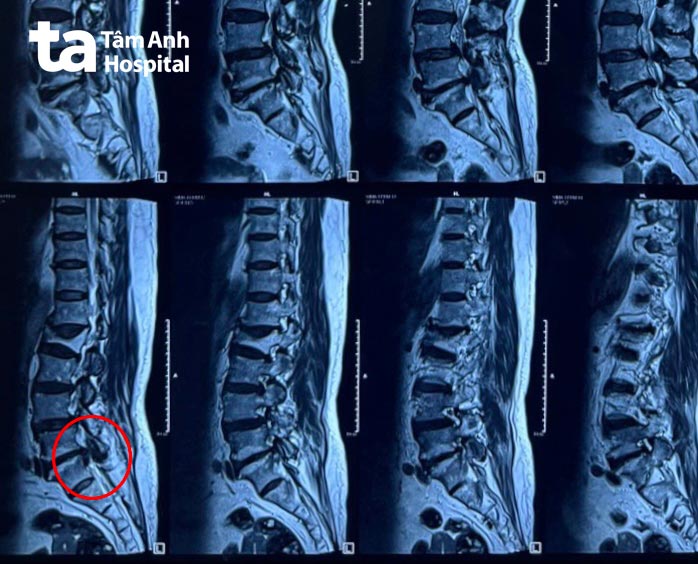

BS.CKI Lê Thanh Vương, khoa Cột sống, cho biết người bệnh bị thoát vị đĩa đệm tầng L5-S1 (vị trí đoạn xương thấp nhất của cột sống, giữa đốt sống thắt lưng thứ 5 và đốt xương cùng thứ nhất), có mảnh rời, khối thoát vị đĩa đệm phì đại chèn ép tầng L4-L5. Trường hợp của cụ Gái, nếu không được điều trị nhanh chóng, có thể dẫn đến đại tiểu tiện không tự chủ, teo dần các chi. Đặc biệt, vì người bệnh cao tuổi, việc hạn chế đi lại và vận động, dẫn đến tăng thời gian nằm một chỗ, làm tăng nguy cơ xuất hiện loét tì đè và huyết khối. Khi huyết khối di chuyển đến các vị trí khác trong cơ thể, có thể gây ra những biến chứng nguy hiểm như thuyên tắc phổi, đột quỵ…

Bác sĩ Vương nhận định, tình trạng thoát vị đĩa đệm của người bệnh đã tiến triển nặng, không thể điều trị bảo tồn, cần phẫu thuật để lấy mảnh rời ra khỏi cơ thể và giải phóng dây thần kinh. Qua đó, giảm đau tê hiệu quả và nhanh chóng khôi phục khả năng đi lại.